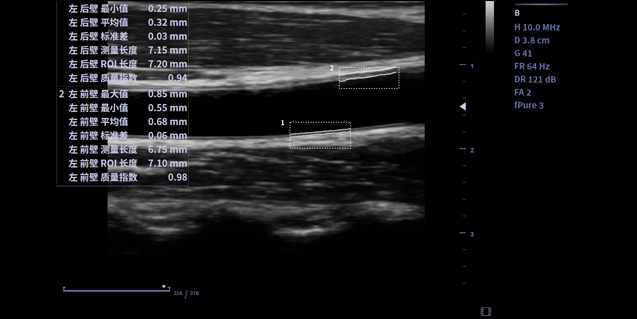

适用于浅表组织、小器官,神经,血管等